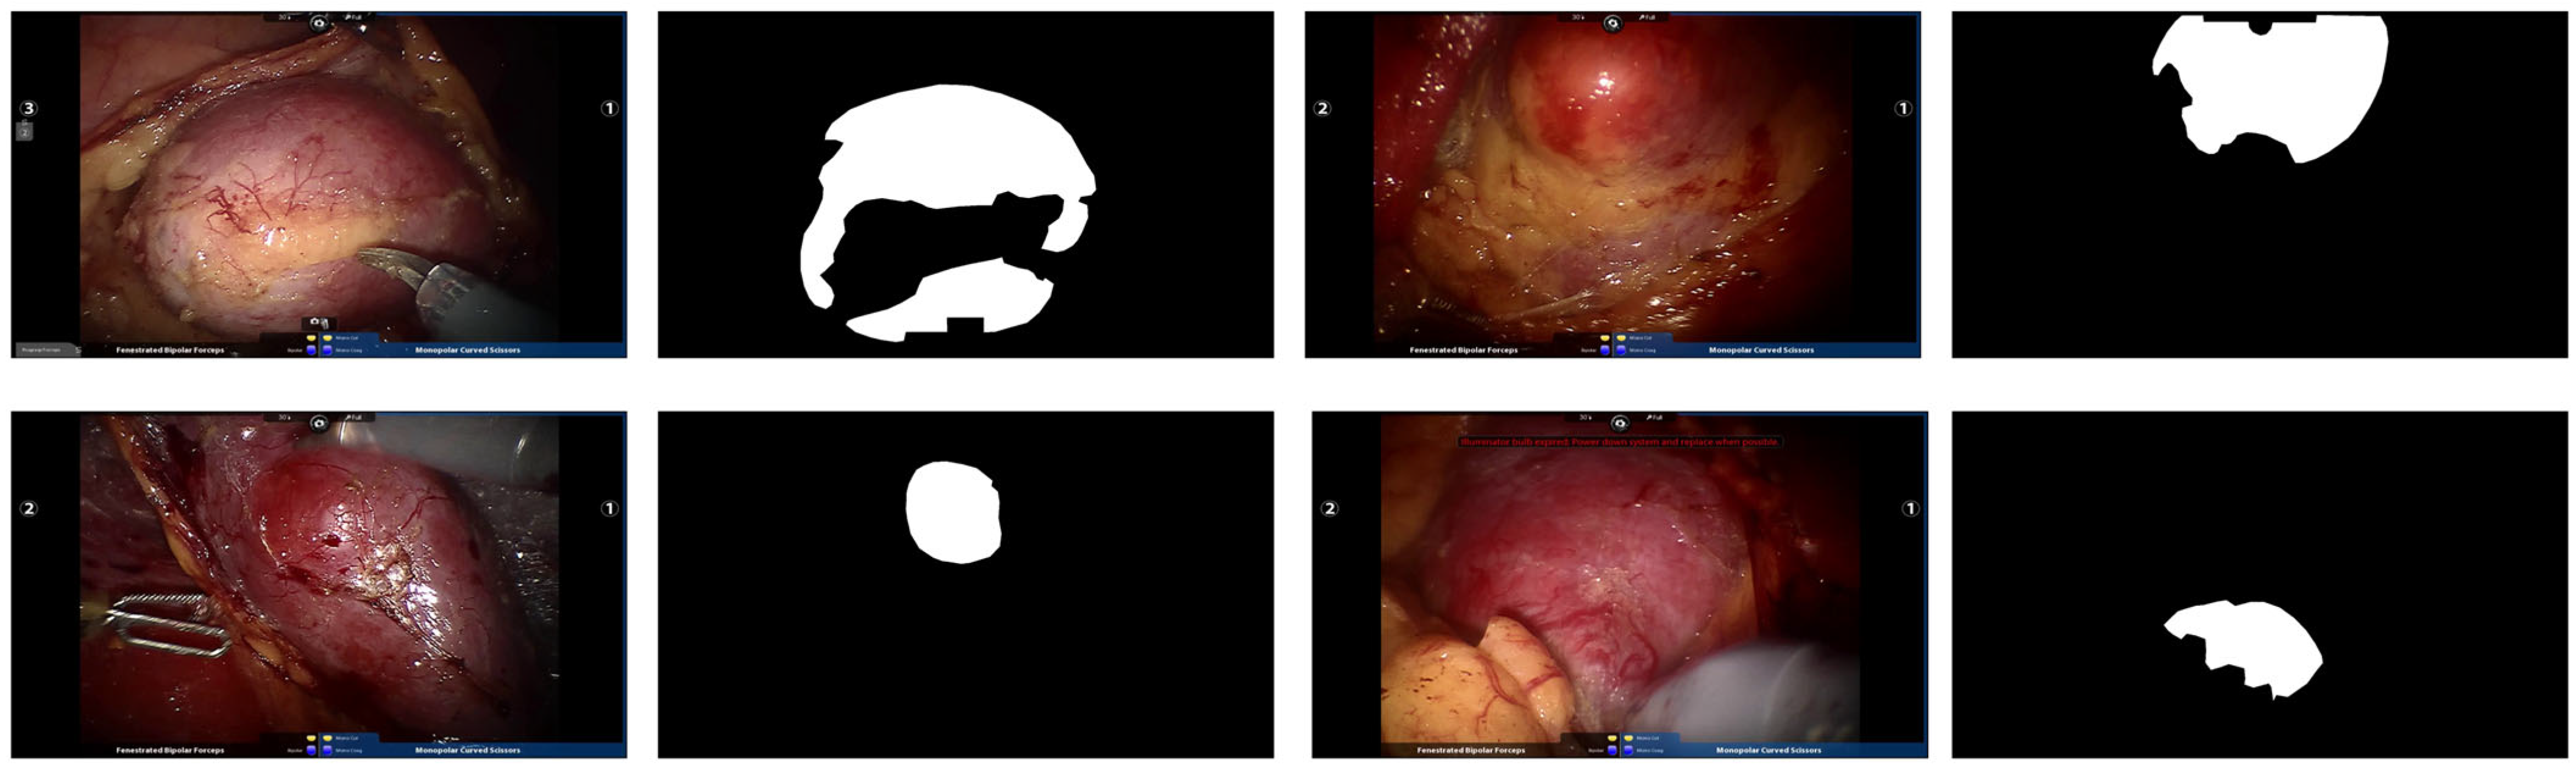

4.2.3. Qualitative Experiments